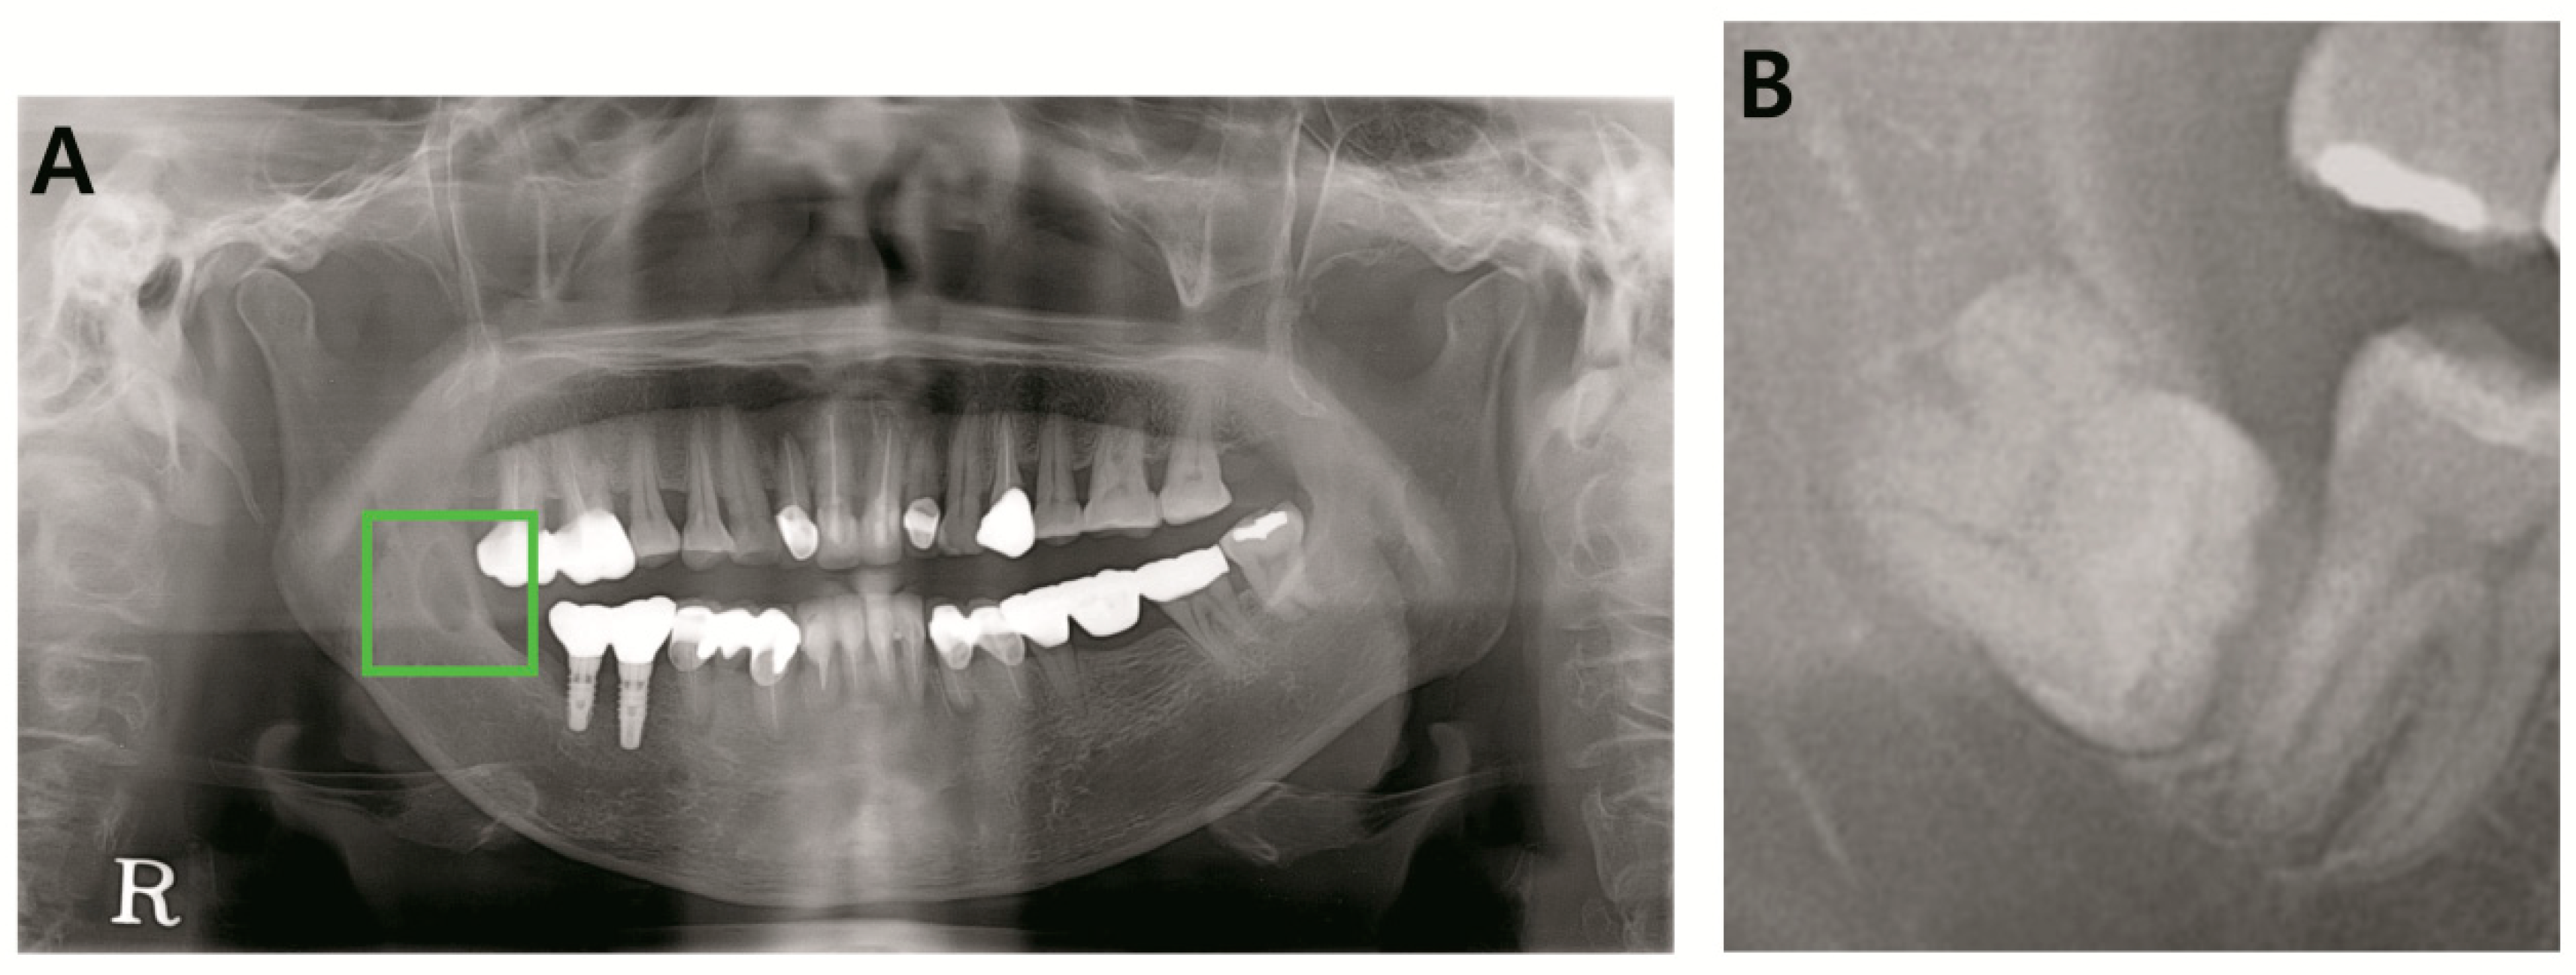

2.2. Annotation of Images

2.3. Pre-Processing and Image Augmentation